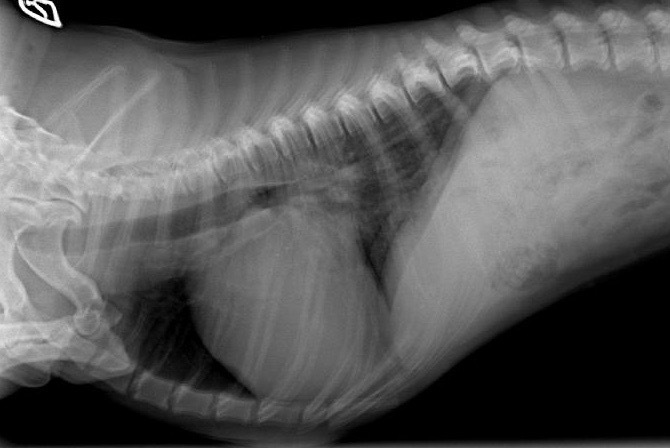

Durch die Herzultraschalluntersuchung konnte dann leider der Verdacht auf eine deutlich weiter fortgeschrittene Herzerkrankung bestätigt werden. Neben einer hochgradigen Vergrößerung der linken Herzhälfte durch die Klappeninsuffizienz ließ sich außerdem ein moderat erhöhter Druck in den Lungenarterien feststellen. Dies nennt man Pulmonale Hypertension oder Lungenhochdruck. Für eine solche Erhöhung des Blutdruckes im Lungenkreislauf gibt es unterschiedliche Ursachen. Eine davon ist ein bestehendes Lungenödem durch ein Linksherzversagen, wie es bei Alf nun offensichtlich der Fall war. Da die Diagnose nun „dekompensierte Mitralklappenendokardiose“ - oder nach der CHIEF - Klassifizierung Stadium C2 * - lautete, verordnete ich dem kleinen Hund zusätzlich zwei weitere Medikamente zur dauerhaften Herztherapie (eines zur Entwässerung und das andere zur Entlastung des Herzens durch Weitstellung der Arterien und zur Unterstützung der Pumpfunktion des Herzmuskels). Die am Morgen im Wald aufgetretene „Synkope“ ließ sich also eindeutig durch die fortgeschritten Herzerkrankung erklären.

Drei Tage später wurde Alf noch zur Röntgenuntersuchung einbestellt, um den Erfolg des Entwässerungsmittels zu überprüfen. Er machte laut Besitzerin einen deutlich muntereren Eindruck und sein Appetit war unter der neuen Herztherapie wieder normal geworden. Die zu Hause ermittelte Ruhe-Atemfrequenz lag bei 22 Atemzügen pro Minute. Da radiologisch aber weiterhin ein leichtes Lungenödem zu erkennen war, wurde die Dosis der „Entwässerungstabletten“ noch etwas erhöht. Zur nächsten Herz-Ultraschall-Kontrolle wurde der Dackel drei Monate später vorgestellt. Er hatte etwas an Gewicht zugelegt, war laut Besitzerin immer „gut drauf“, zeigte durchgehend eine normale Atmung und hatte keine weitere Synkope. Die Befunde am Herzen waren stabil, nur wurde im mitlaufenden EKG nun eine zusätzliche Herzrhythmusstörung festgestellt, sogenannte Vorhof-Extrasystolen. Die Herztherapie wurde daher um ein antiarrhythmisch wirkendes Medikament ergänzt. Unter dieser Therapie verlebte Dackel Alf einen fröhlichen Sommer inklusive Dänemarkurlaub. Da zwischendurch die Ruhe-Atemfrequenz ein wenig angestiegen war, wurde die Dosis der „Entwässerungstabletten“ noch etwas erhöht. Bis zur nächsten kardiologischen Kontrolle weitere sechs Monate später lag diese dann immer im normalen Bereich zwischen 16 und 20 Atemzügen pro Minute und auch die Ultraschallbefunde waren weiterhin stabil.